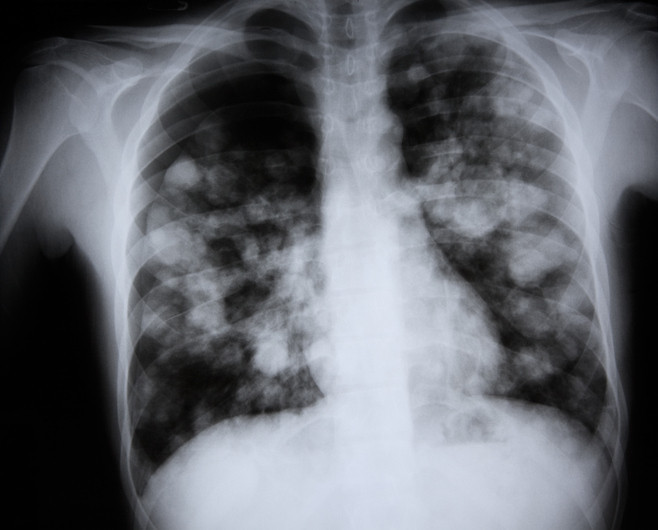

Zatürre, akciğerlerdeki küçük hava keseciklerini etkileyen bir göğüs enfeksiyonu olarak tanımlanıyor. Hastalar nefes almakta zorlanabilir, bazı durumlarda kan öksürebilir veya solunum cihazına bağlı olarak yaşam mücadelesi verebilirler. İngiltere ve Galler’de 2024 yılında 23.061 kişinin yaşamını yitirdiği istatistiklerde, zatürre ve grip birlikte ölüme neden olan en önemli faktörler arasında gösteriliyor.

Hunter, grip virüsünün üst solunum yollarına saldırarak, bu bölgedeki mikroskobik tüyler olan siliyalara zarar verdiğini ifade etti. Bu tüyler, akciğerlerdeki alveol adı verilen hassas hava ceplerine yerleşen bakterileri ve zararlı parçacıkları uzaklaştırmakla görevlidir. Siliyalara zarar gelmesiyle akciğerler bakterilere karşı savunmasız hale gelir. Alveoller enfekte olduğunda sıvı, kan veya irinle dolar ve oksijenin kan dolaşımına geçmesi neredeyse imkânsız hale gelir.

Zatürre belirtileri arasında hırıltı, öksürük ve akciğerlere yeterli hava girememe bulunur. Bu durum, hayati organların temel işlevlerini yerine getirmesini zorlaştırır. Zatürreye bağlı en ciddi komplikasyon ise sepsistir; kanın enfekte olup toksik hale gelmesi, çoklu organ yetmezliğine ve ölüme yol açabilir.